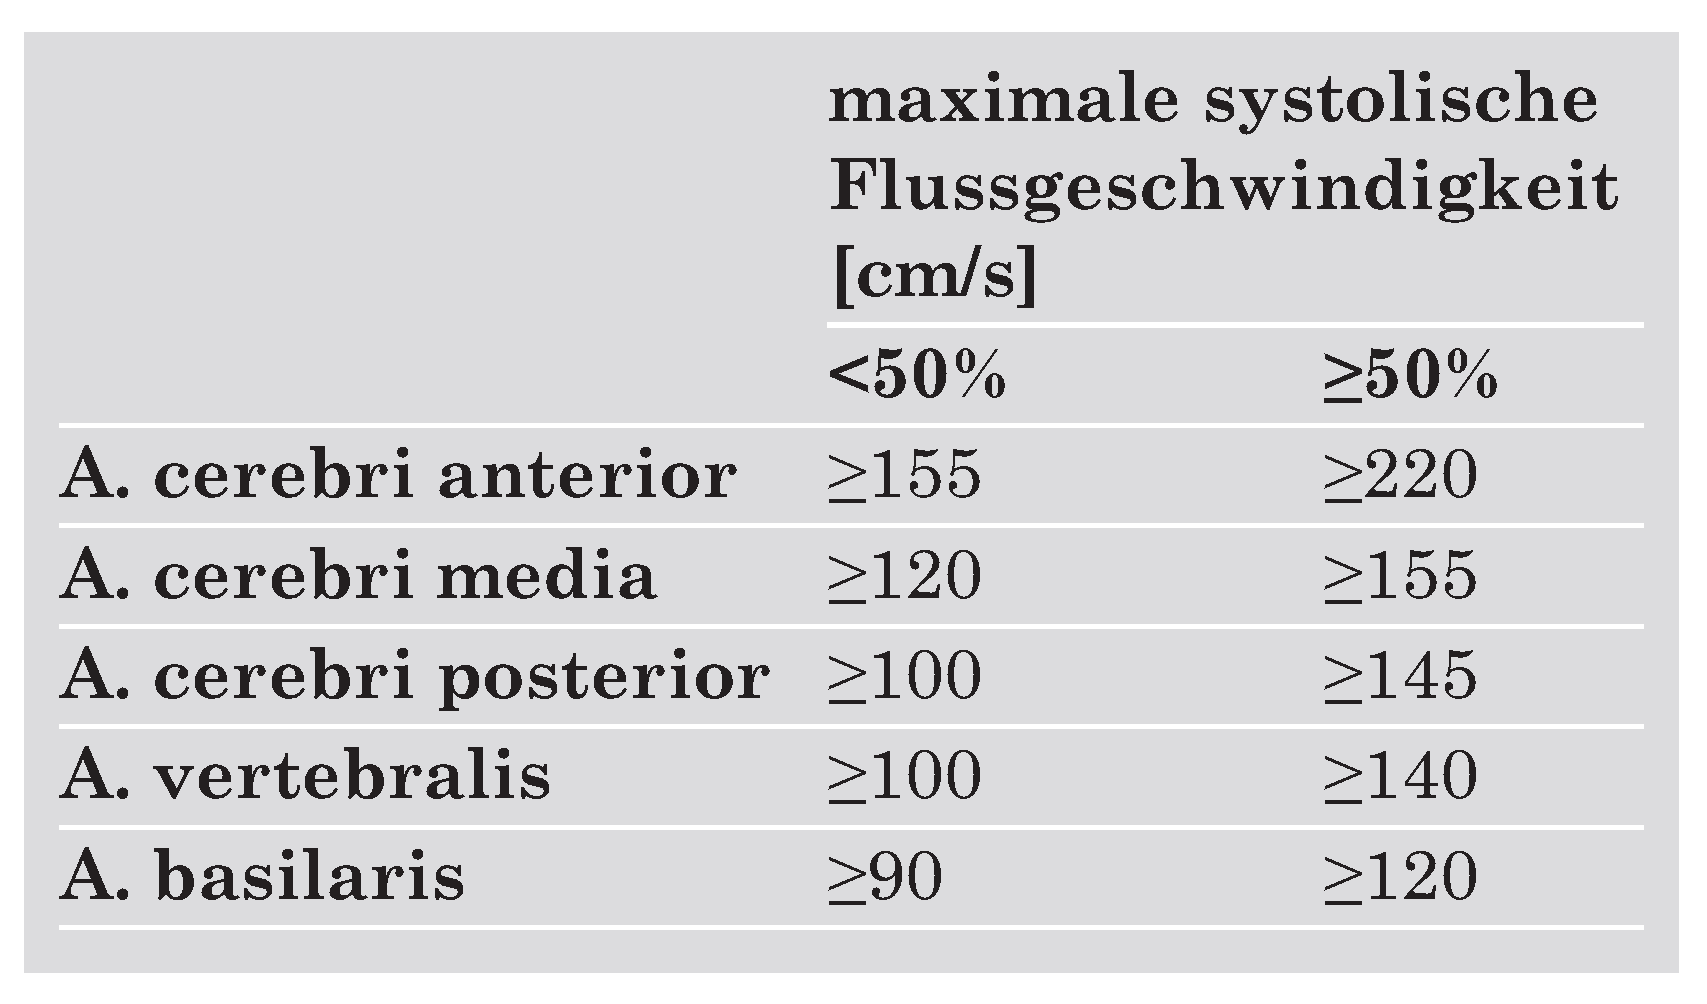

Ultrasonographische Verfahren